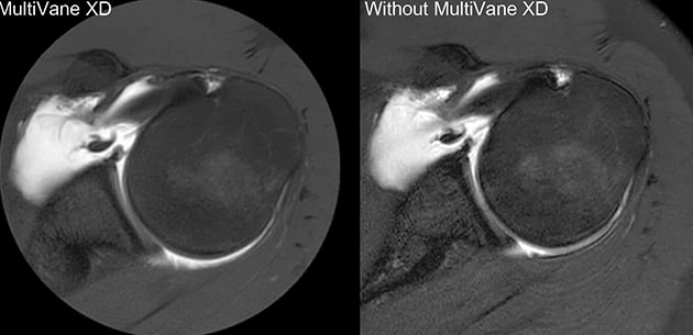

Comparison of axial fat suppressed PD-weighted imaging with (left) and without (right) MultiVane XD in the left shoulder demonstrates imaging with MultiVane XD provides excellent image quality, even in presence of motion.